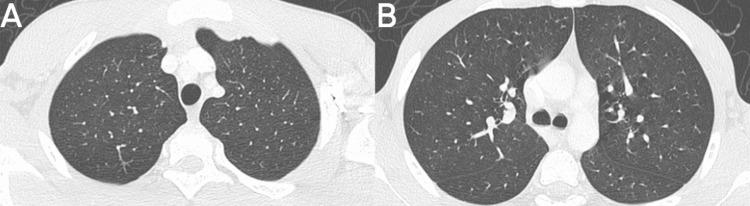

Daptomycin-induced eosinophilic pneumonia (DIEP) is a rare but serious complication associated with the use of this broad-spectrum antibiotic. We present the case of a teenager with a history of nasopharyngeal cancer who developed DIEP while receiving daptomycin to treat an infection associated with an implanted chamber catheter. Symptoms included recurrent dyspnea and peripheral eosinophilia, with radiological findings consistent with DIEP. The pathophysiology involves an immune response triggered by daptomycin, resulting in eosinophilic pulmonary inflammation. Diagnosis requires a thorough evaluation of medical history, clinical laboratory tests, and radiological findings. The main treatment involves discontinuation of daptomycin and, in severe cases, the use of steroids. It is essential to consider DIEP in patients with respiratory failure and bilateral pulmonary opacities who have used daptomycin and to suspect it in those with blood eosinophilia or in bronchoalveolar lavage.

达托霉素诱导的嗜酸性粒细胞性肺炎(DIEP)是一种与使用这种广谱抗生素相关的罕见但严重的并发症。我们报告了一名有鼻咽癌病史的青少年病例,该患者在接受达托霉素治疗与植入式腔静脉导管相关的感染时发生了DIEP。症状包括反复出现的呼吸困难和外周血嗜酸性粒细胞增多,影像学检查结果与DIEP一致。其病理生理学涉及由达托霉素触发的免疫反应,导致嗜酸性粒细胞性肺部炎症。诊断需要对病史、临床实验室检查和影像学检查结果进行全面评估。主要治疗方法包括停用达托霉素,在严重病例中使用类固醇。对于使用过达托霉素且出现呼吸衰竭和双侧肺部混浊的患者,必须考虑DIEP,对于有血嗜酸性粒细胞增多或支气管肺泡灌洗的患者应怀疑有DIEP。